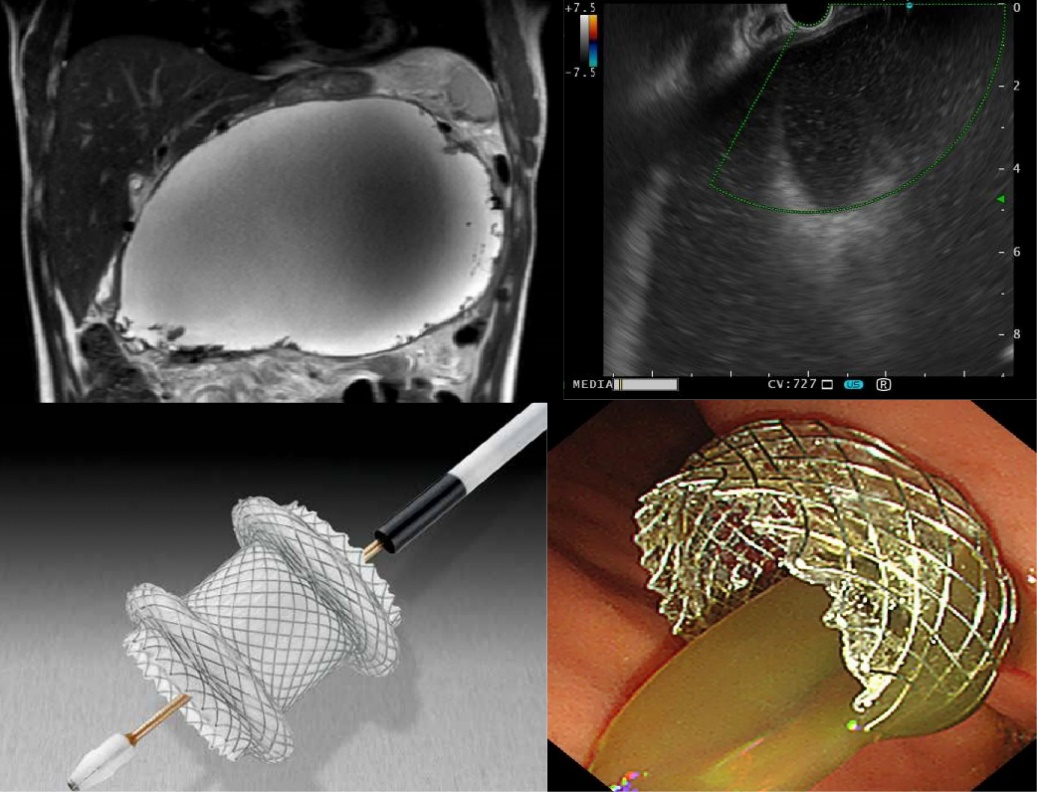

诊疗特色:慢性肝病、肝硬化、脂肪肝、自身免疫性肝病、重症肝炎、胆道结石、肝胆胰肿瘤等肝胆胰疾病一站式诊断综合治疗;内镜下肝胆胰微创诊断及手术,如超声内镜引导下肝胰腺穿刺活检,胆总管取石术、胆管胰管支架置入术、各种胆胰术后吻合口狭窄治疗;人工肝治疗技术等。

△利用超声内镜下电切引流支架置入术(Hot AXIOS)治疗胰腺巨大假性囊肿